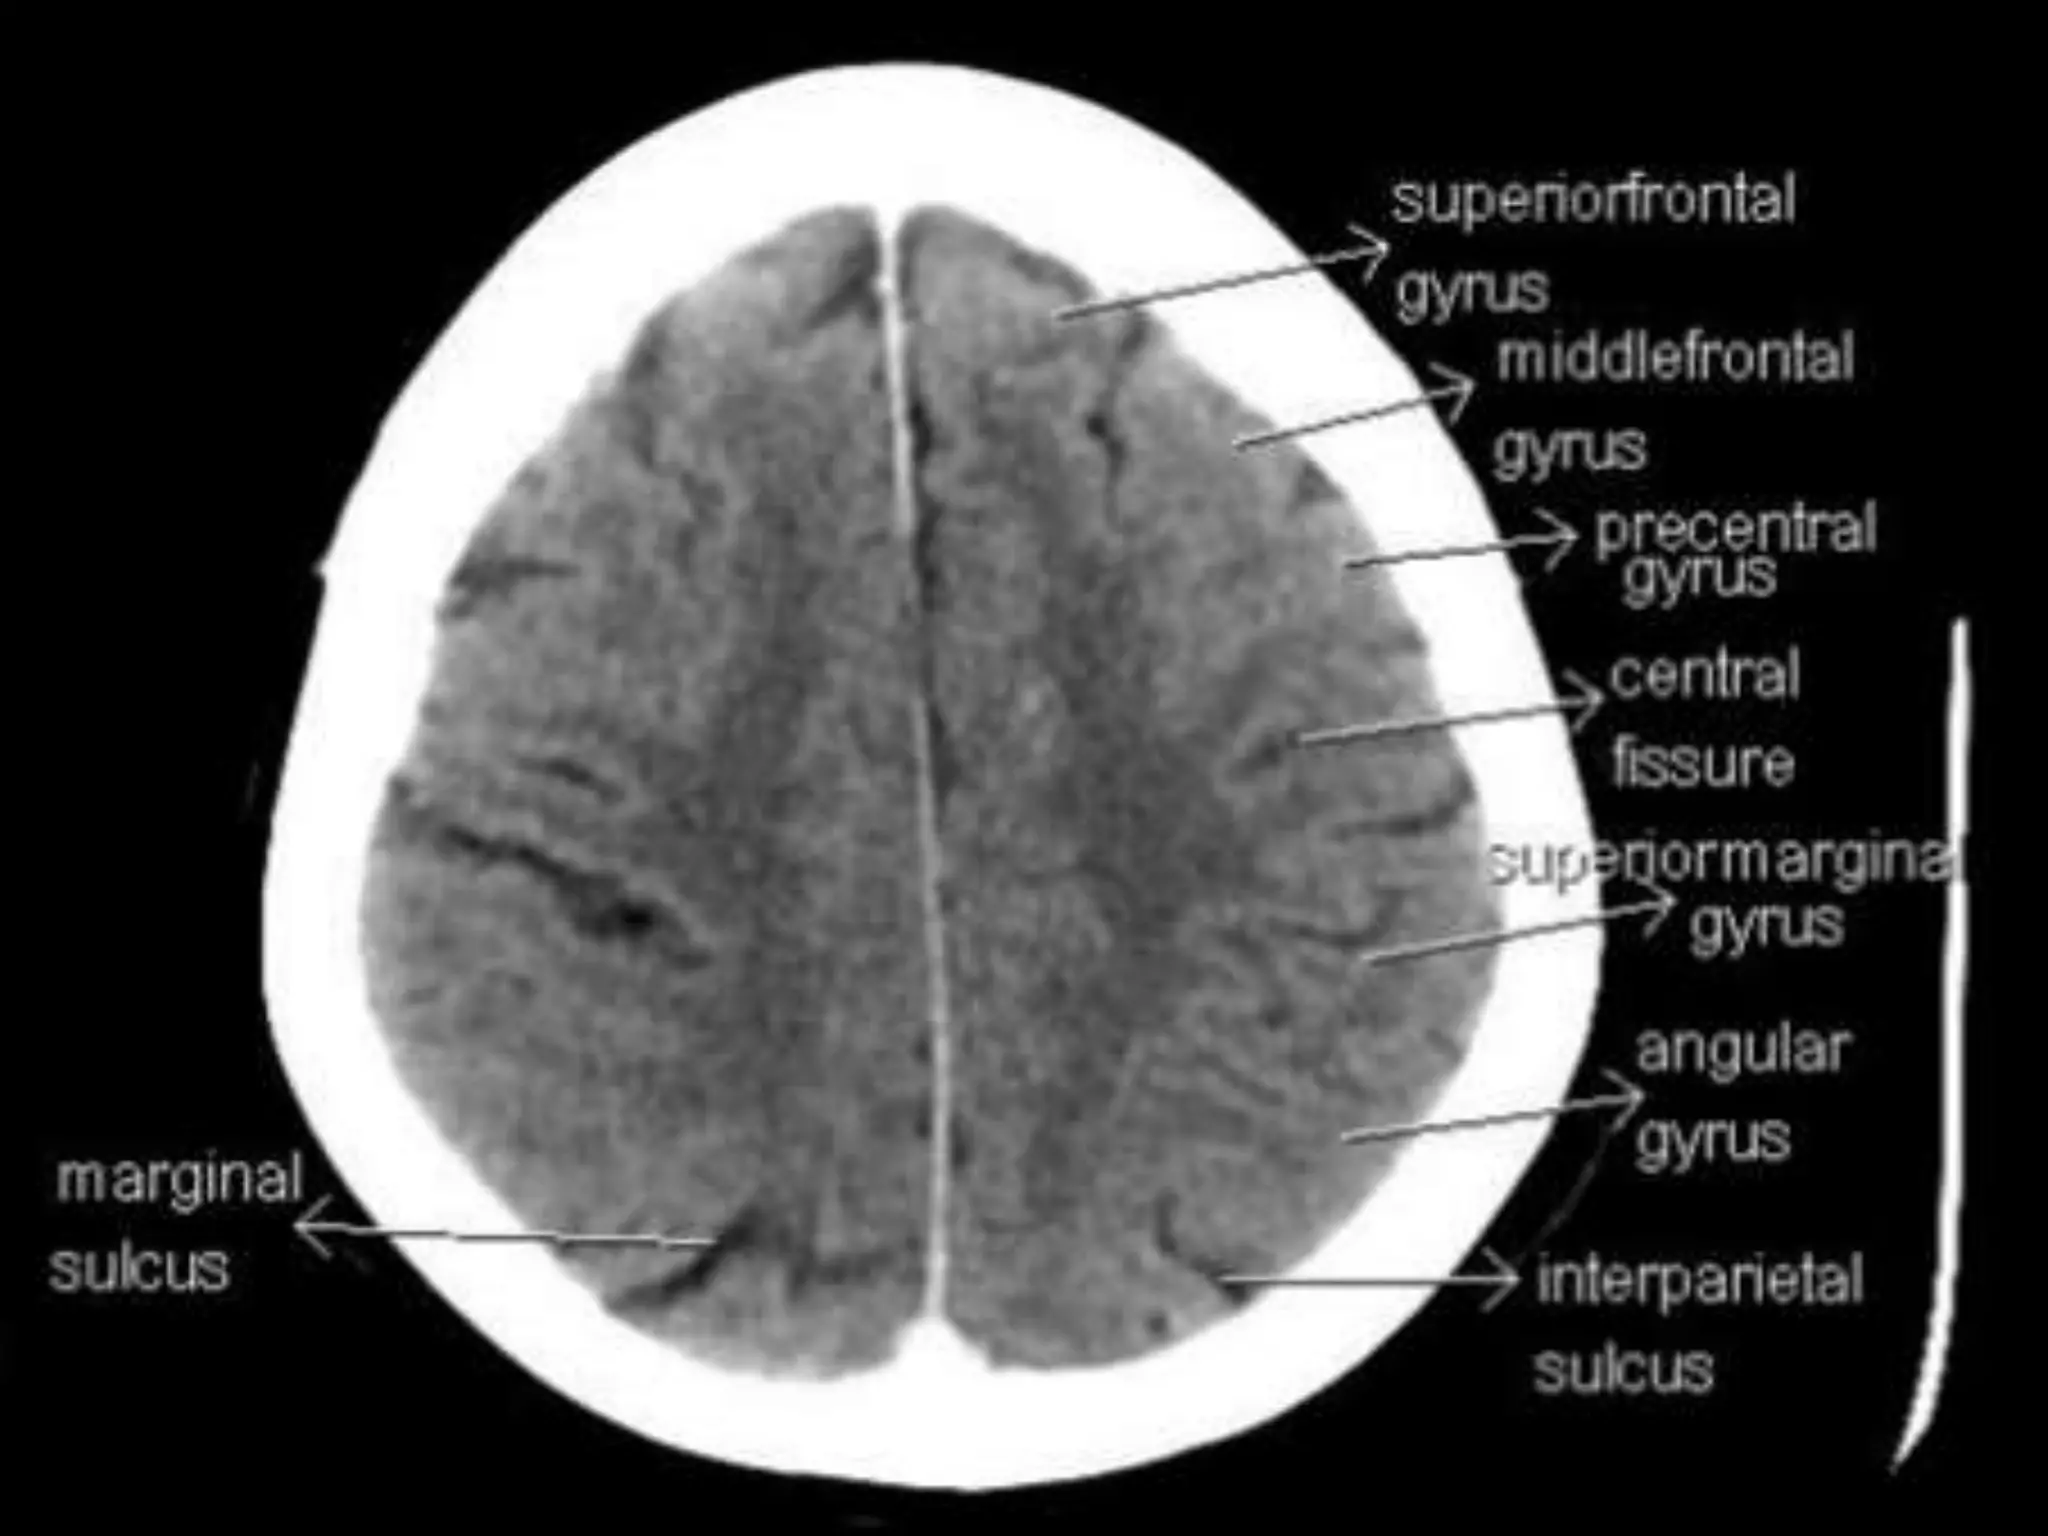

The two cerebralhemispheres are separated by interhemispheric fissures and falx cerebri. On the lateral surface of the brain, the sylvian fissure (lateral fissure) and the rolandic fissure (central fissure) separate the cerebral hemisphere into the frontal lobe, temporal lobe, parietal lobe, and a line drawn from the parieto-occipital sulcus onto the preoccipital notch, delineating the boundaries of the parietal and temporal lobes from that of the occipital lobe. The frontal lobe, the largest of all the brain, has four principal gyri: the precentral gyrus and the superior frontal, middle frontal, and inferior frontal gyri. The precentral gyrus, parallel to the central sulcus, together with the anterior bank of the central sulcus, comprises the primary motor area, which is one of the most important cortical areas for movement. Rostral to the precentral sulcus is the premotor area, another important area for movement. The middle frontal gyrus contains Brodmann’s area 8, known as the frontal eye field, which is important for conjugate eye movements. Another important motor area for speech called Broca’s area, is located at the triangular and the opercular parts of the inferior frontal gyrus in the dominant hemisphere.